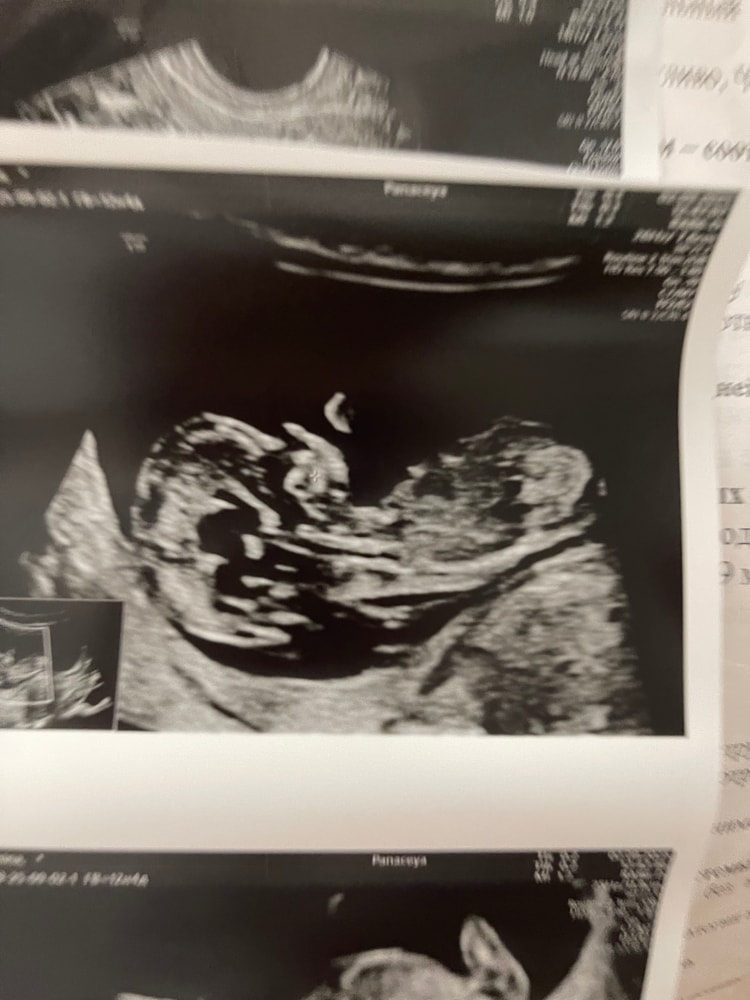

Анализы, скринингиУзи. По месячным срок 11, 5. По УЗИ поставили 12 и 6. Немного напугало ТВП - 2,10, носовая кость визуализируется. В целом все хорошо ттт, завтра сдаю кровь.